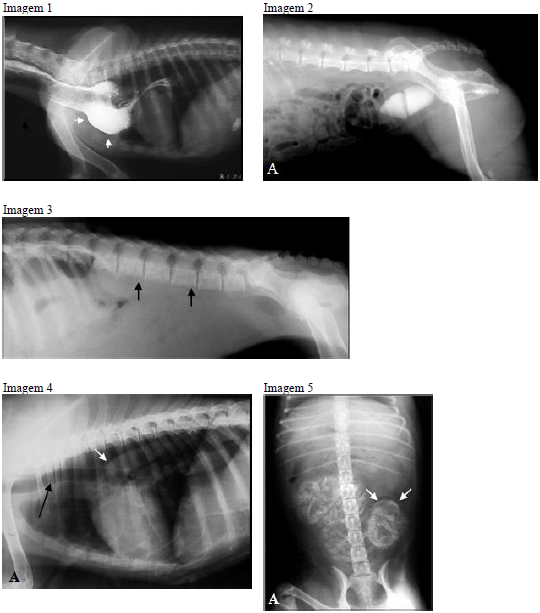

De acordo com as imagens radiográficas de cães, apresentadas abaixo, assinale a alternativa correta.